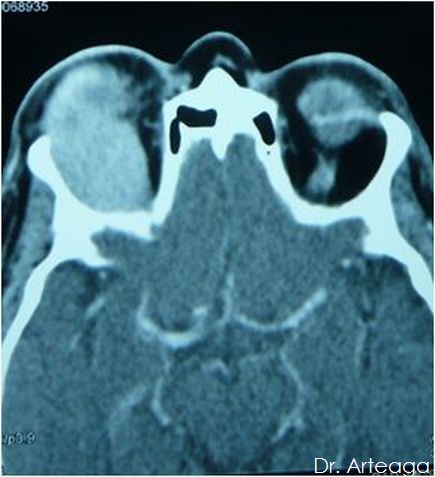

Galería de Imágenes